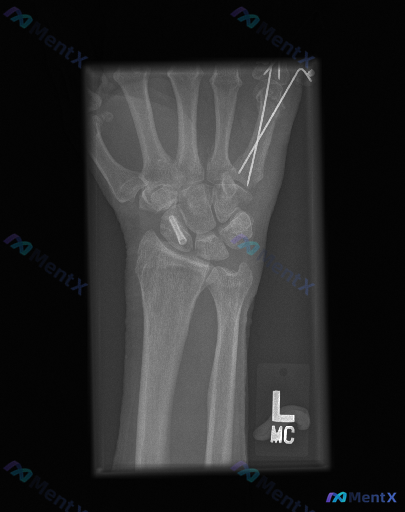

整理到一份左腕术后的复查影像资料,想和大家讨论一下当前的优先级判断方向。 基本背景:左腕创伤术后,本次复查左手腕正位X光片。 影像所见: 1. 内固定物:舟骨腰部可见一枚金属螺钉,位置大致沿舟骨长轴;第一掌骨基底部与大多角骨附近可见两枚交叉克氏针,针尾部延伸至软组织外/影像边缘。 2. 骨折与骨骼:...